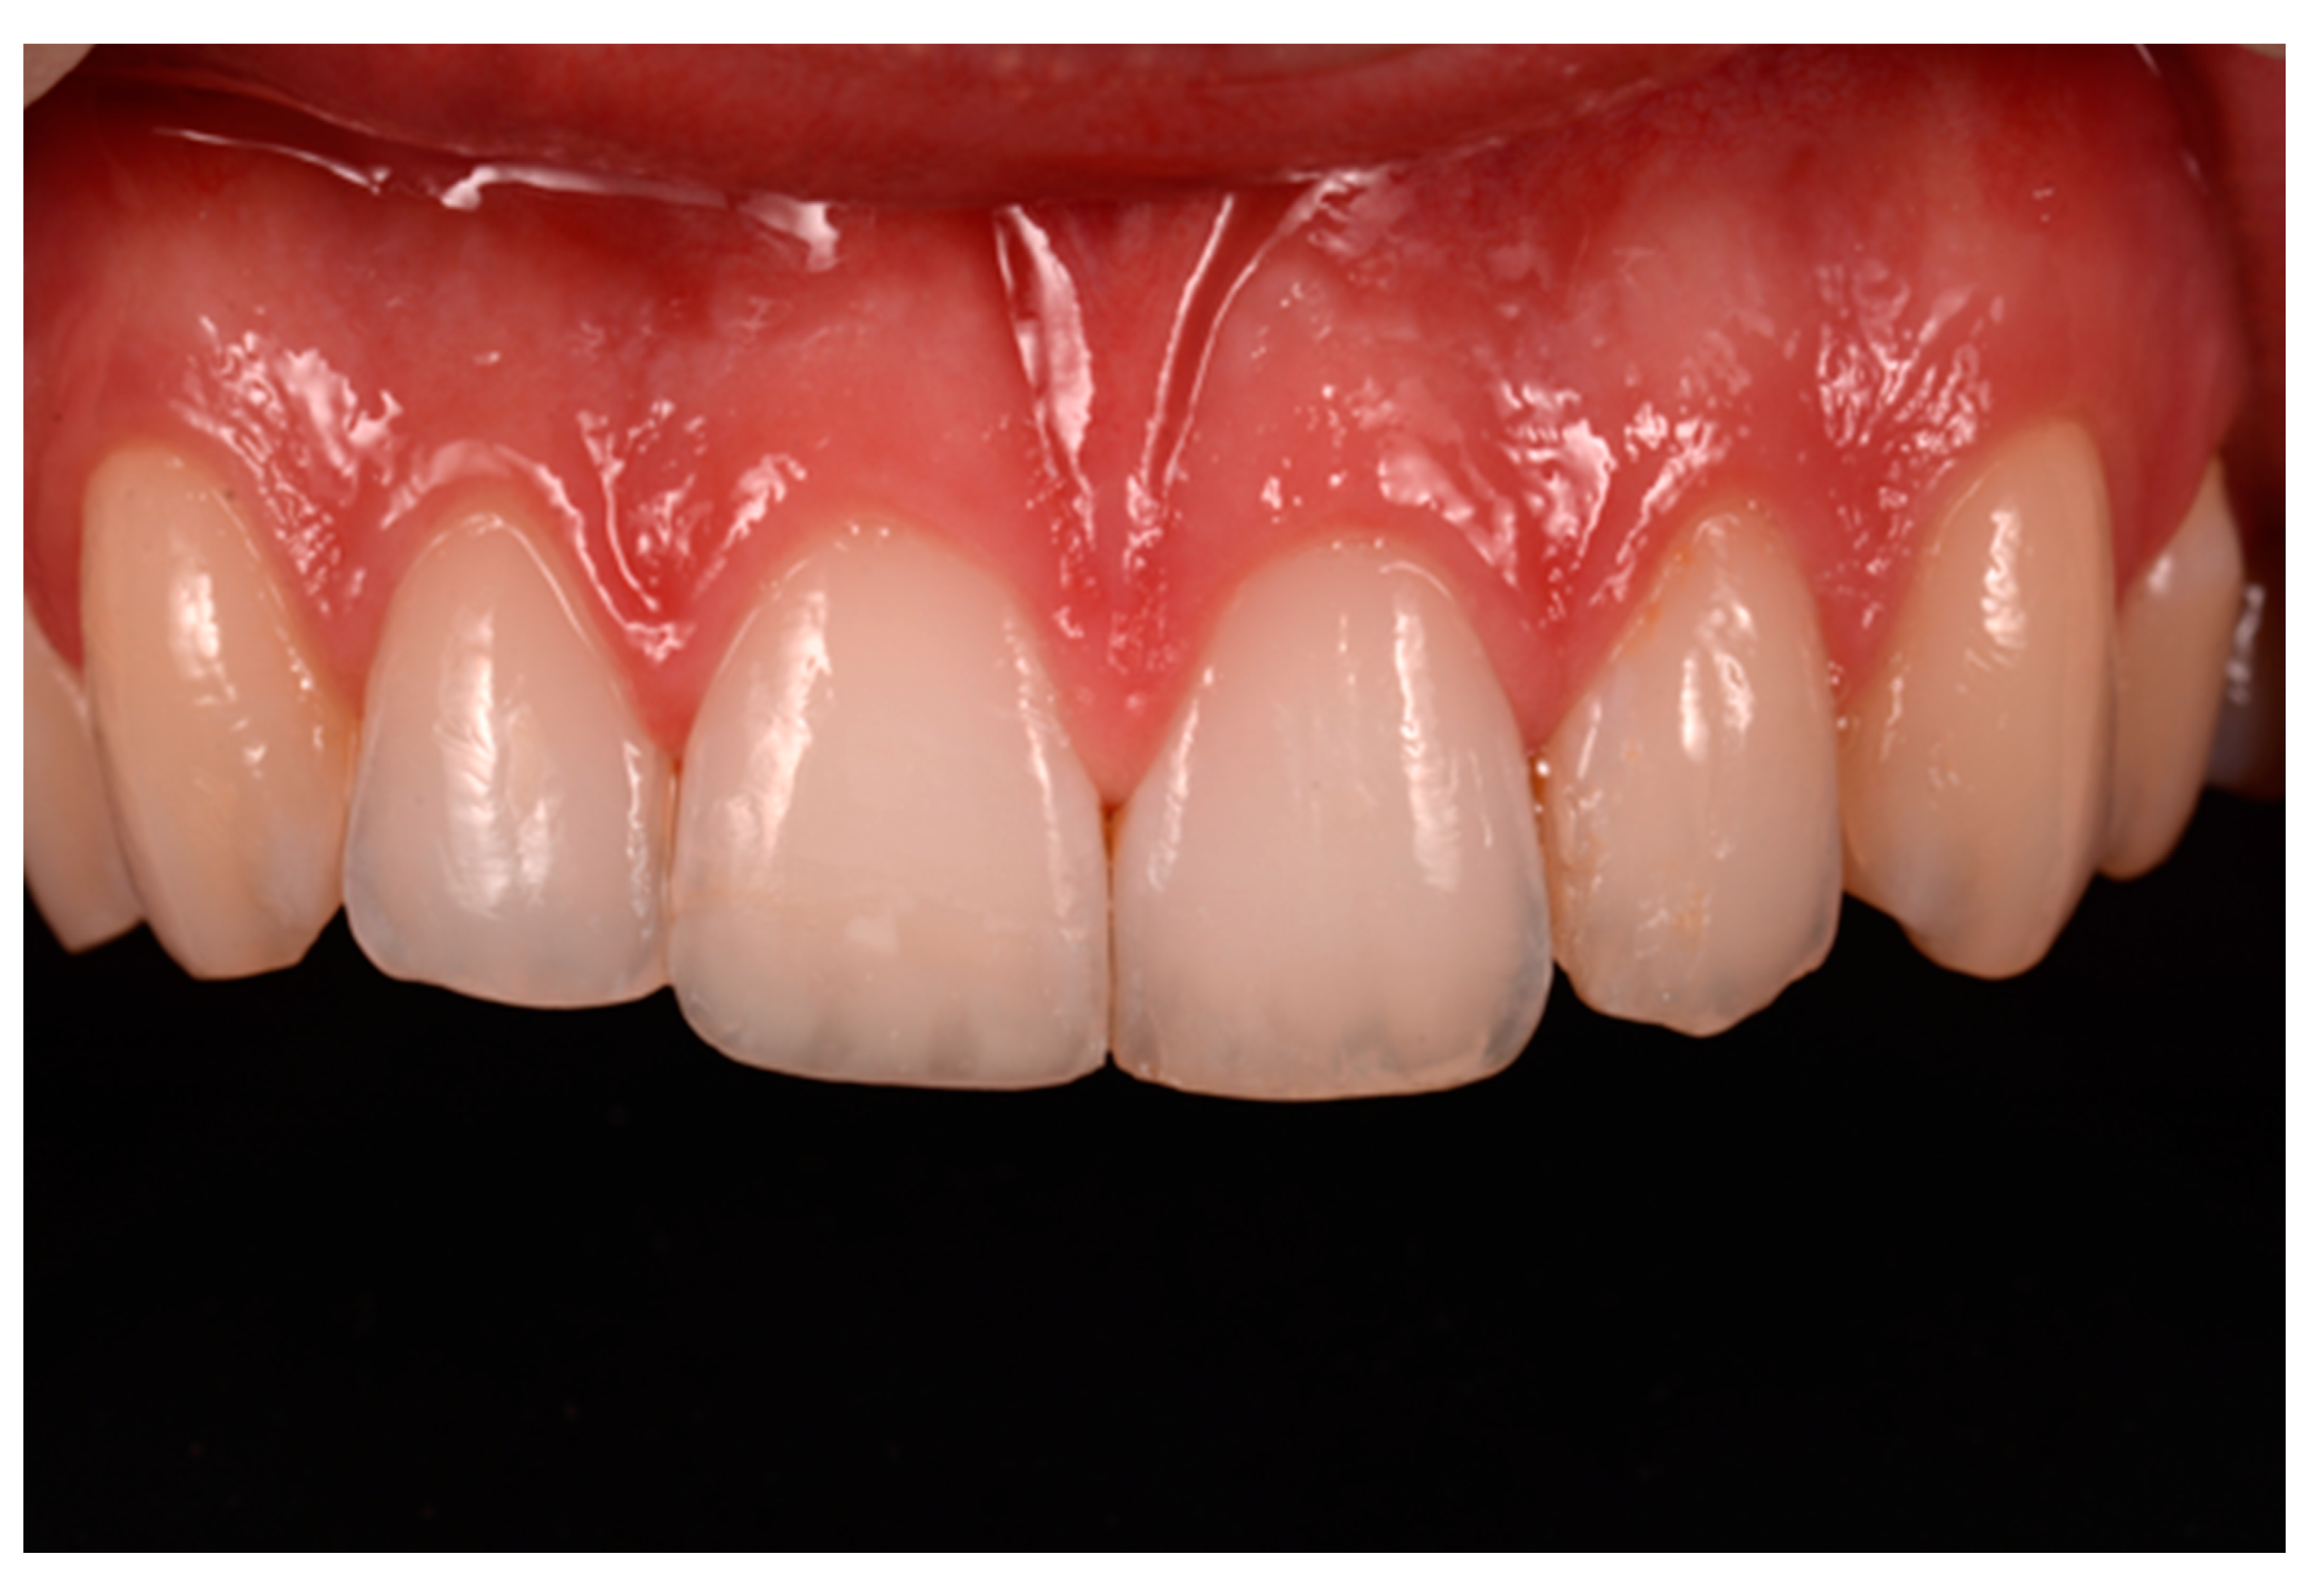

Finishing and polishing procedures were performed with a diamond bur (WL 268 014 Horico, Berlin, Germany), silicone points (Identoflex, Kerr, Bioggio, Switzerland) brushes (Jiffy Goat Air Brushes, Ultradent Products, South Jordan, UT, USA), and diamond pastes (Diamond Polish Mint, Ultradent Products, South Jordan, UT, USA) (Figure 13 and Figure 14). Satisfactory clinical and radiographic outcome was considered satisfactory at 3-months, 1-year, and 5-years post-operative (Figure 15, Figure 16, Figure 17, Figure 18 and Figure 19).

Figure 15.

Three months post-operative. Reprinted from Restauri diretti nei settori anteriori, G. Paolone, S. Scolavino, © 2021, with permission from Quintessence Publishing Italy.